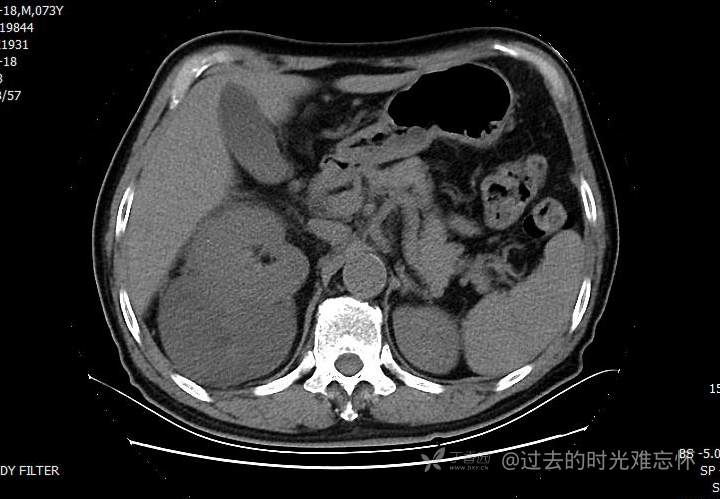

患者性别:男

患者年龄:73岁

主诉:咳嗽1月余。曾有血尿一次。后背部酸痛不适1-2年左右,无明显消瘦。

辅助检查:CT MRI

临床诊断:占位

治疗经过:手术